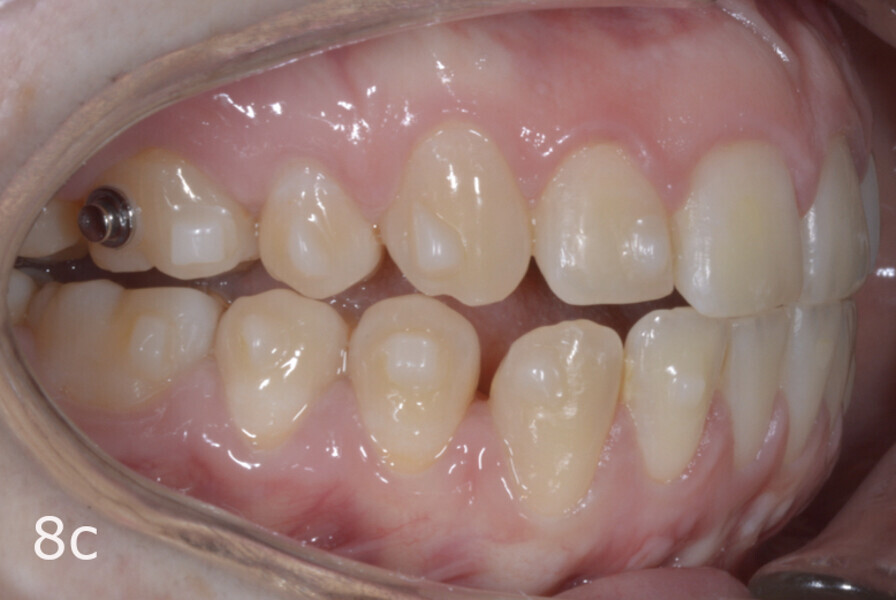

The treatment objectives included closing the anterior open bite, achieving a bilateral Angle Class I relationship and a proper overjet and overbite, correcting the midline discrepancies, and achieving a profile harmonisation. The treatment plan consisted of orthodontic camouflage treatment with asymmetric distalisation in three of the four quadrants using Invisalign aligners (Align Technology) and third molar extraction. The Invisalign Comprehensive package was chosen, and 63 pairs of aligners were used (Figs. 7–10). Each aligner was worn for 20 hours a day for one week each. The use of Class III elastics on both sides was indicated. Afterwards, ten refinement aligners were needed to improve the interdigitation on the right side (Figs. 11 & 12).

Although Class III elastics tend to extrude the maxillary molars and generate clockwise mandibular rotation, aligners allow us to prevent these complications, since we have better control over tooth movement, enabling us to counteract unwanted dental movements. In this case, an intrusion of the posterior teeth was planned, which would generate anticlockwise rotation of the mandible in an anticlockwise direction. This vertical control led to the closure of the anterior open bite and the reduction of the lower facial height, thereby improving the facial profile.

The total treatment time was 15 months. An Angle Class I relationship was established along with adequate anterior and canine guidance, establishing a functional occlusion. This not only ensures optimal masticatory function but also protects the teeth and the temporomandibular joint from excessive force. Maxillary and mandibular fixed retention were installed at the end of the treatment (Figs. 13–19).